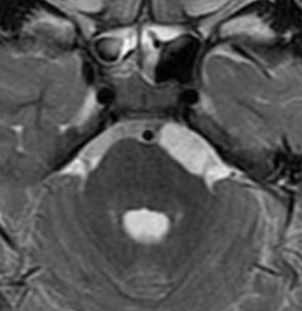

МРТ головного мозга. Т2-взвешенная аксиальная МРТ. Эпидермоидная киста в области предмостовой цистерны слева.

Эпидермоидные кисты (эпидермоиды) - доброкачественные врождённые образования. Они происходят из эктопических эпидермальных клеток и развиваются в период закрытия, в 3-5 нед. эмбриогенеза, как следствие неполного разделения нейрональной и покровной эктодермы. Частота составляет около 1% от внутричерепных образований. Обычно диагностируются в возрасте 25 - 45 лет. Локализация эпидермоидов может быть любой, но типичная - мосто-мозжечковый угол (третье по частоте образование этой области), предмостовая цистерна, параселлярная область, четверохолмие и желудочковая система, очень редко в полушариях, спинном мозге и интрадиплоидно. Растут они интра- или экстрадурально, экспансивно, медленно, сдавливая ствол мозга, внутричерепные нервы, но не разрушая кость. Иногда захватывают сосуды и нервы. По характеру роста их можно отнести к опухолевидным образованиям. Вокруг эпидермоидов нередко развивается асептическое воспаление, а при разрыве содержимое (жир, кератин) прорывается в ликворные пространства. Клинические проявления зависят от локализации и масс-эффекта.

При МРТ головного мозга картина неспецифическая и зависит от содержимого кисты. Если она не содержит жира, топри МРТ головного мозга эпидермоидная киста имеет ликворную интенсивность сигнала. В таком случае эпидермоидная киста трудно отличима от арахноидальной, хотя, как правило, не столь однородная. На FLAIR томограммах и диффузионно-взвешенных МРТ головного мозга содержимое эпидермоидов светлее ликворного. Жировое содержимое, такие эпидермоиды еще называют холестеатомой, приводит к высокому сигналу на Т1-зависимых МРТ головного мозга. Видимо, он обусловлен липидами, но не холестеролом. На Т2-взвешенных МРТ головного мозга он менее интенсивен чем ликвор. Контуры эпидермоидов на МРТ всегда четкие. Холестеатомы составляют всего 3-5% от эпидермоидов. В 15-20% случаев встречается кальцификация по переферии кисты. Редко наблюдается усиление стенок кисты при МРТ головного мозга с контрастированием.